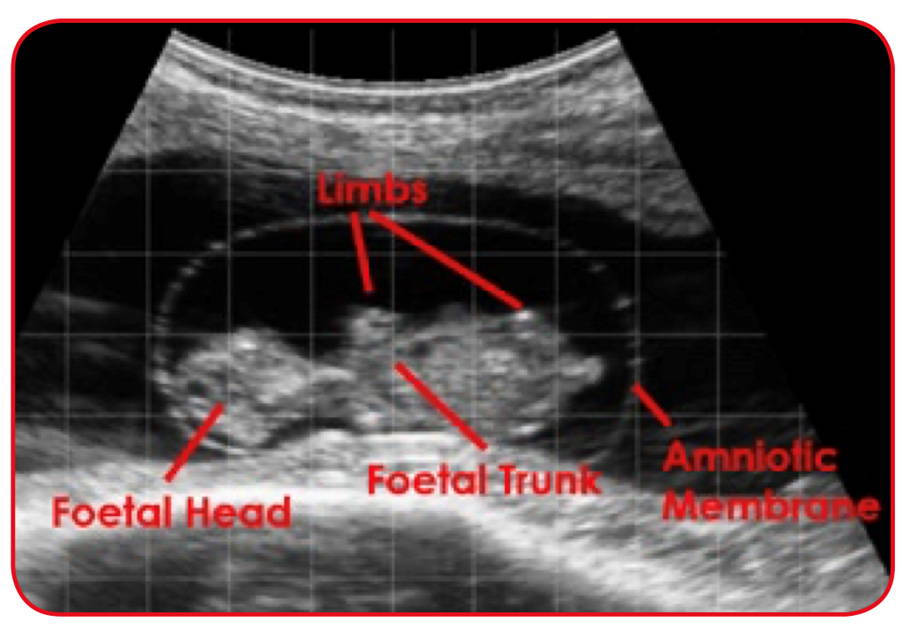

Continuing our diagnostics articles, this week I thought it would be interesting to cover the most common diagnostic technique we use in practice – ultrasound. My favourite farmer description is that ‘it’s like looking at an out of tune tv’, hopefully the fuzzy black and white pictures will make more sense after this! Physics play the vital role in our scanners. The probe (sometimes called the transducer) contains ceramic crystals (piezoelectric crystals) which can produce sound waves when an electric current is applied to them. The frequency used is above the hearing capability of the human ear. These sound waves then spread out through the area being scanned and depending on the density of the tissue they hit are reflected at different intensity.

Rather cleverly, the crystals can work in reverse, when a returning sound wave hits them, they can generate an electric current. This current is used to produce a black and white image on the fashionable goggles you see us sporting. The greater the number of sound waves reflected, the stronger the electric signal and the brighter white the image will appear:

White = very solid surfaces such as cartilage or bone, due to most of the sound waves being returned.

Grey = medium return of waves, soft tissues such as the uterus and ovaries are grey.

Black = most commonly fluid, this returns very few waves. Gas will also appear as black on the screen, as the waves are not reflected back by gas at all.

As such, we can pick out certain features of the foetus depending on the age. At 30 days they are the size of a jellybean, but as soon as 40 days when can start to pick out the head and legs. Further into the pregnancy other body features become clearer such as ribs, stomach, small intestine etc. This ability to pick out foetal features means scanning is superior to other ways of diagnosing pregnancy in cattle. We can see the foetal heartbeat from 30 days, meaning we have conclusive proof that the foetus is viable, whereas some of the hormone tests will still remain high for a couple weeks after the foetus has expired.